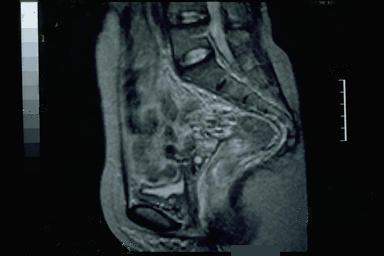

Criteria of Hist.ClassificationMalignant epithelial tumor/Signet-ring cellcarcinoma

LocationLarge intestine(Colon)/Rectum

Technique, MethodMRI

Macroscopic TypesType 3 Ulcerated type with infiltration/

Size35 - 40

Depth of Tumor Invasionserosa (adventitia)